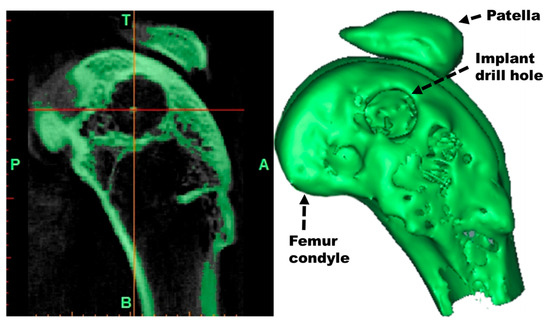

2.4. Densitometric Analysis with µ-CT and 3D Reconstruction